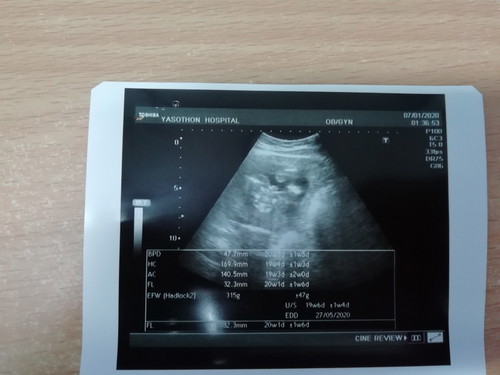

วันนี้ไปโรงพยาบาลมา เลยอยากทราบว่า เป็นผู้ชาย หรือ ผู้หญิงค่ะ 20 week